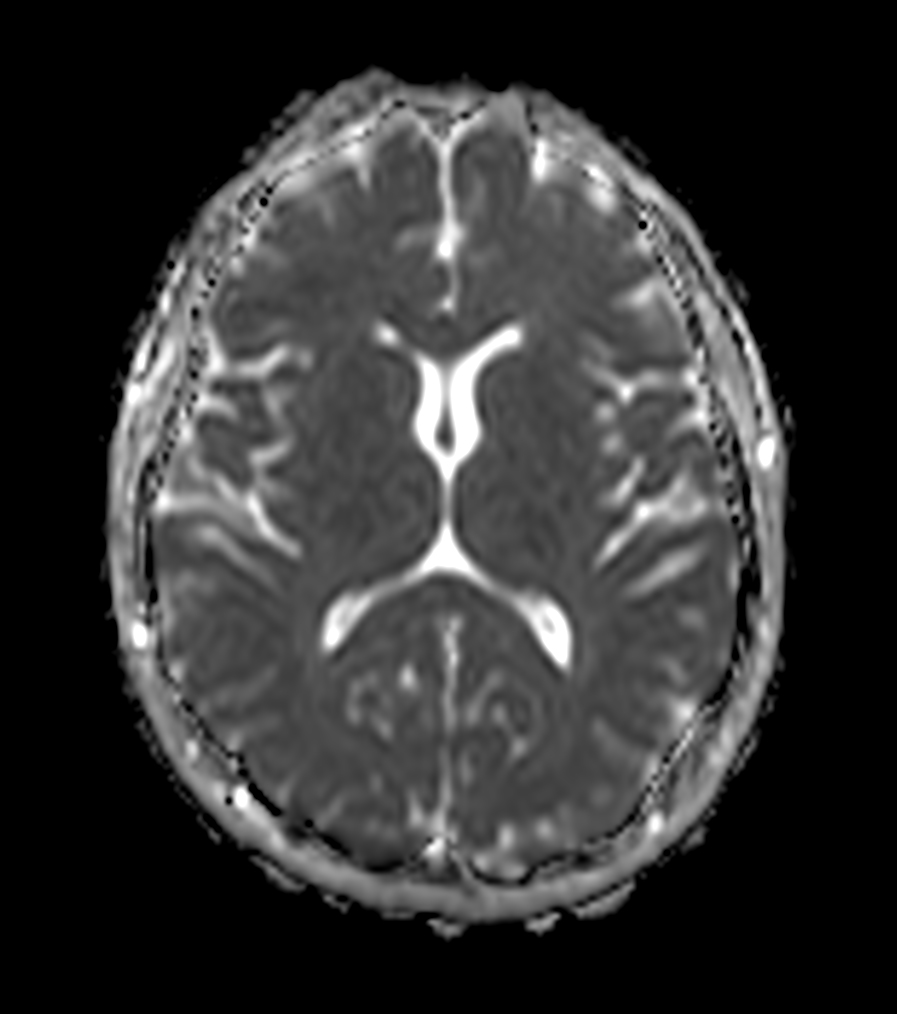

Axial T2w TSE MultiVane XD